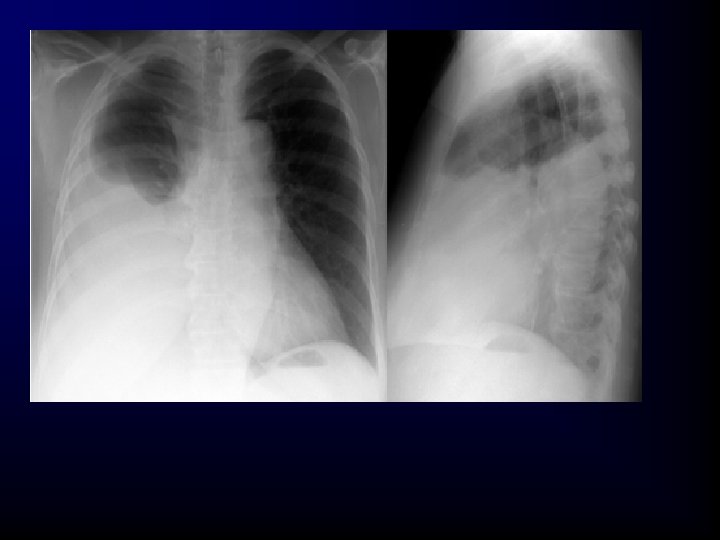

Pulmonary Injury • Closed (simple) pneumothorax – Incidence • 10% to 30% in blunt chest trauma • Almost 100% with penetrating chest trauma – Morbidity/mortality • Extent of atelectasis • Associated injuries – Pathophysiology • Caused by the presence of air in the pleural space • A common cause of pneumothorax is a fractured rib that penetrates the underlying lung.

Closed (Simple) Pneumothorax • May occur in the absence of rib fractures from: – A sudden increase in intrathoracic pressure generated when the chest wall is compressed against a closed glottis (the paper-bag effect) • Results in an increase in airway pressure and ruptured alveoli, which lead to a pneumothorax • Small tears self-seal; larger ones may progress. • The trachea may tug toward the affected side. • Ventilation/perfusion mismatch.

Closed Pneumothorax Assessment Findings • • Tachypnea Tachycardia Respiratory distress Absent or decreased breath sounds on the affected side Hyperresonance Decreased chest wall movement Dyspnea Chest pain referred to the shoulder or arm on the affected side • Slight pleuritic chest pain

Closed Pneumothorax Management • Airway and ventilation – High-concentration oxygen. – Positive-pressure ventilation if necessary. – If respiration rate is <12 or >28 per minute, ventilatory assistance with a bag-valve mask may be indicated.

Closed Pneumothorax Management • Nonpharmacological – Needle thoracostomy • Transport considerations – Position of comfort (usually partially sitting) unless contraindicated by possible spine injury